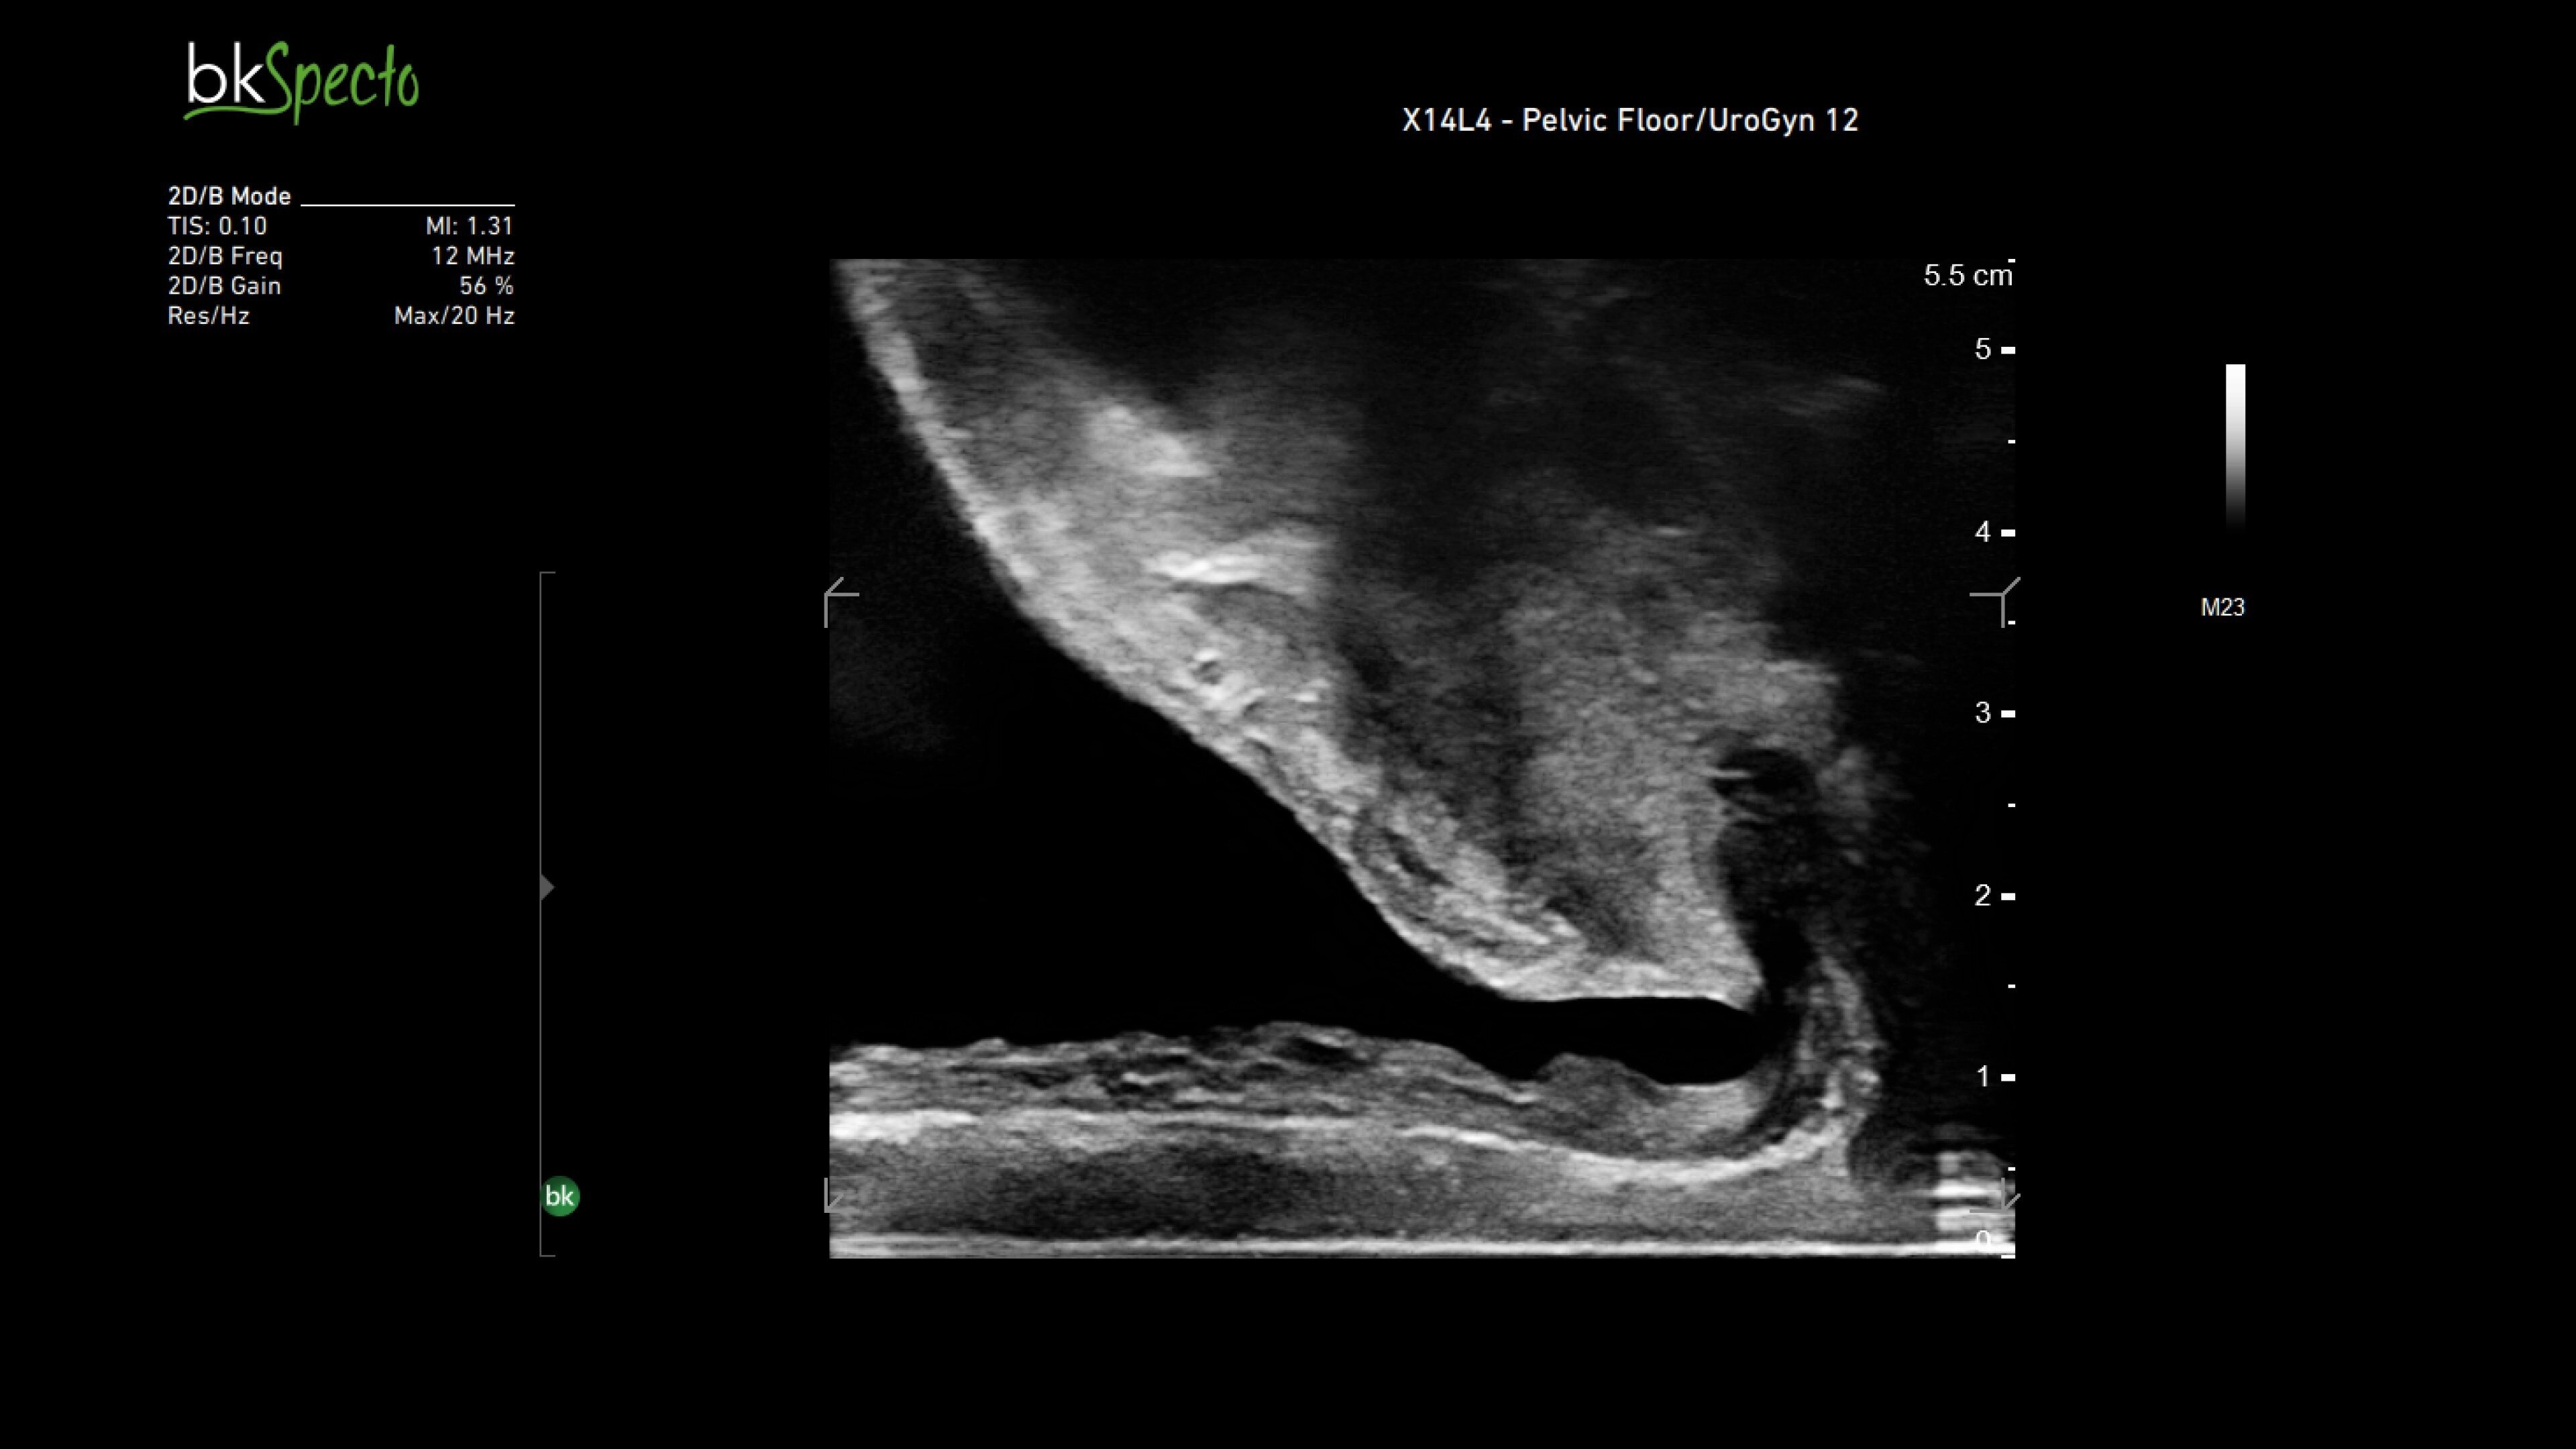

The bkActiv ultrasound system delivers remarkable imaging for general surgery, including anorectal, robotics-assisted, and pelvic floor surgeries. Its advanced algorithms provide uniform image resolution and greater detail, while the remote control allows surgeons to adjust images within the sterile field. For anorectal surgeries, bkActiv offers high-definition imaging to visualize normal and abnormal anatomy, including anal sphincter injuries and rectal cancer. In robotics-assisted surgeries, the system's robotic transducers provide real-time, high-resolution imaging to locate and assess lesions and critical structures. For pelvic floor surgeries, bkActiv's advanced 3D architecture supports dynamic, real-time examination during procedures.